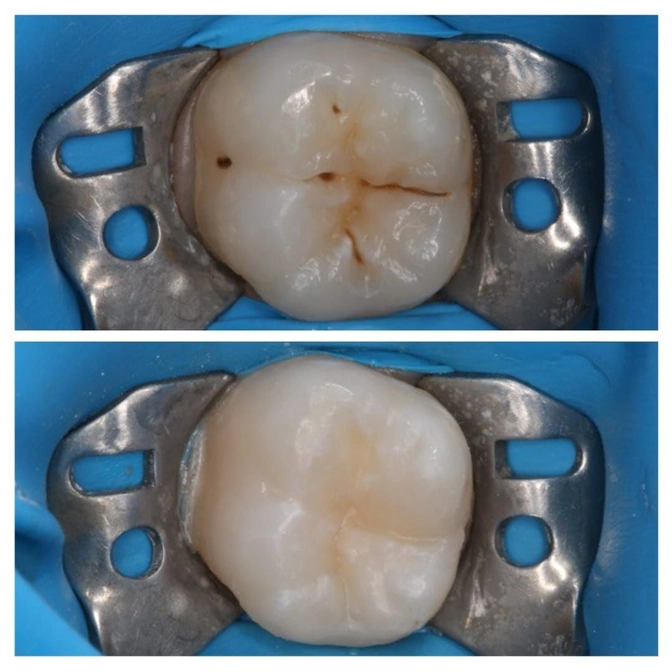

Лечение кариеса у 6-летки

Конечно же это привело к кариесу на "шестерке".

✔️Зуб изолирован коффердамом (это вон тот синий латексный платочек, который защищает рабочую область от попадания слюны и влажного дыхания);

✔️Пораженные кариесом ткани убраны;

✔️Зуб отреставрирован пломбировочным материалом.